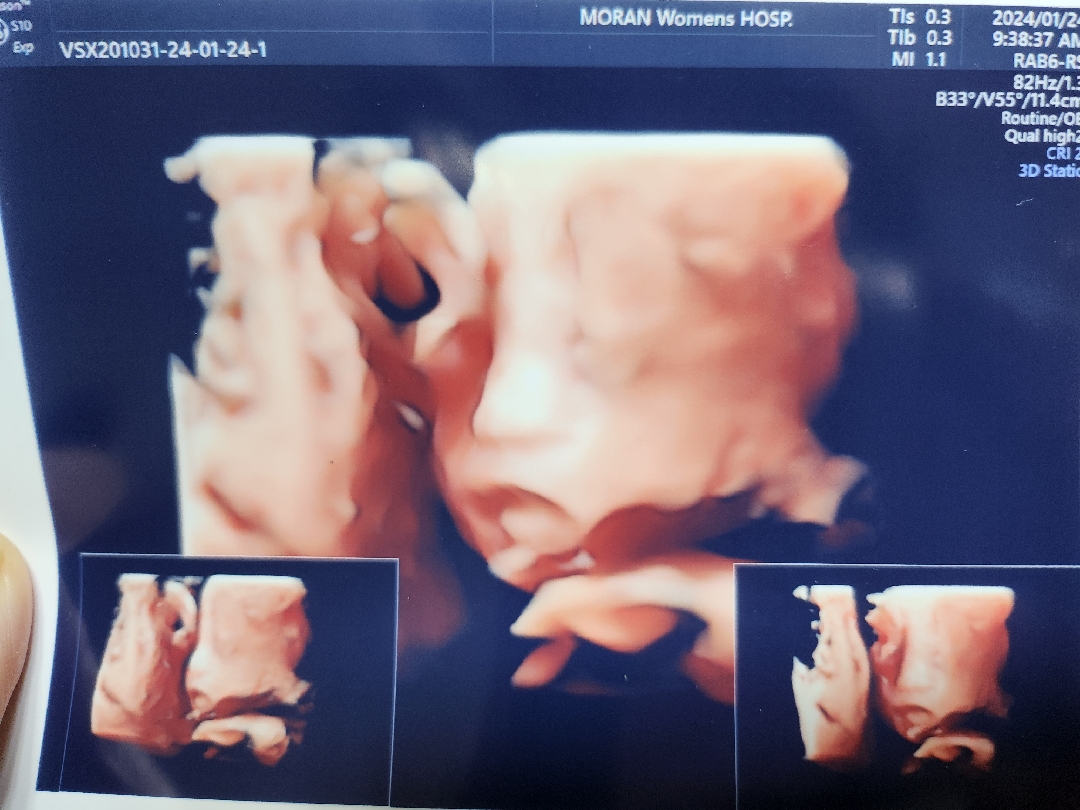

24주 2일에 임당 검사 후 아들 얼굴 보구 왔어요😊

저번에는 아들이 부끄러웠는지 한손을 올리고 있어서 보지 못했어요ㅎ 어제도 한손과 다리를 올린 채 보여주지 않았지만 그래도 제가 움직이고 하니까 조금씩 얼굴을 봤어요ㅎ 얼굴을 보구 오니까 걱정이 사라졌어요😊 아들 얼굴이 귀엽게 생겼고, 신기했어요ㅎ 28주에 정밀초음파가 있는데 그때는 제대로 볼 수 있겠죠😊